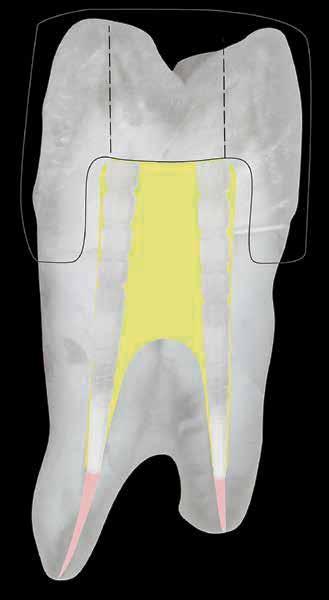

Post preparation of the root canal space must not remove additional dentin, as this contributes to a reduced fracture toughness. (Fig. 1)

Figure 1 Especially in ovoid canals (which are the norm) post preparation needlessly remove dentin and result in weakening the remaining tooth structure, leaving lateral gutta percha which compromises bonding/cementation.

Figure 1 Especially in ovoid canals (which are the norm) post preparation can needlessly remove dentin and result in weakening the remaining tooth structure, while leaving lateral gutta percha which compromises bonding/cementation.

Figure 1 — Especially in ovoid canals (which are the norm) post preparation can needlessly remove dentin and result in weakening the remaining tooth structure, while leaving lateral gutta percha which compromises bonding/cementation.